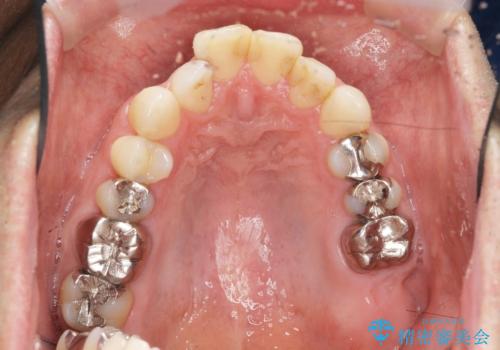

- 突き出た前歯の角度の改善と虫歯治療の改善を求めて来院されました。

虫歯を除去したのち、マウスピース矯正治療を行い、歯並びやがたつきを改善したのち、セラミックに置き換えることで審美性の向上を計画します。

矯正や虫歯治療、セラミック治療といった複合的な治療を一医院で行うことができるのが当法人の大きな特長です。